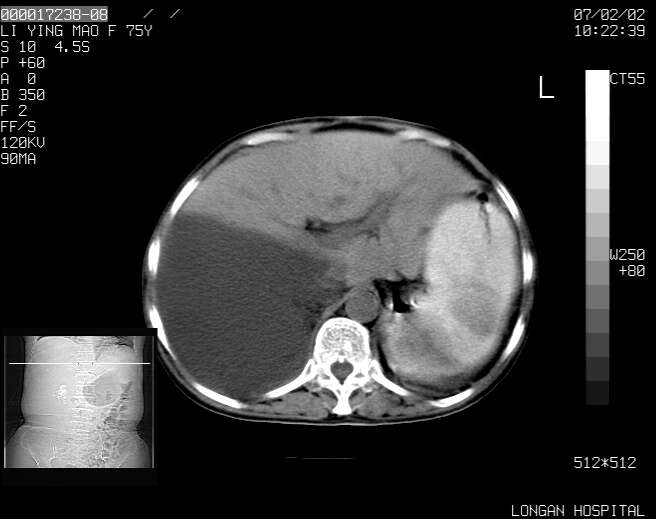

以下是引用dyqct在2007-2-10 8:53:00的发言:[br]考虑:1、肝脏多发囊肿[br] 2、左肾囊肿,右肾多发结石并积水。[br] 3、右胸少量积液。[br] 4、右肾周包裹性积液或淋巴管瘤(有见缝就钻的征象、薄隔、小结节状钙化)?[br] 5、腰椎动脉瘤样骨囊肿?[br] [br] [br]